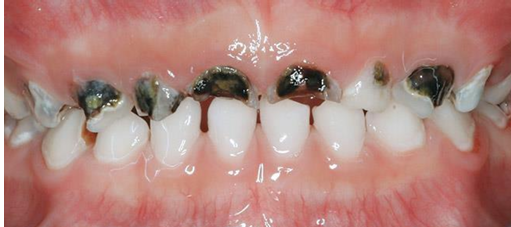

MFD EXAMS /23 6 1234567891011121314151617181920212223 You have 30 min to complete this exam. The timer will start once you begin Attention: Only a few minutes left! Please submit your answers soon. MFD 1 Get a quick sneak peek before the real exam !This trial quiz is designed to show you the question style, difficulty level, and how the options will appear on the platform. 1 / 23 1. What is the lethal dose and toxic dose of fluoride, management? Check 2 / 23 2. What the advantage of silver diamine over other methods and disadvantages ? Check 3 / 23 3. Method of topical fluoride application with concentration ? Check 4 / 23 4. What will happen if left untreated? Check 5 / 23 5. What changes that will happen if the habit stopped? Check 6 / 23 6. Give 3 of your initial stage of treatment? Check 7 / 23 7. What are the causes? Check 8 / 23 8. What is this? Check 9 / 23 9. Then they specified the type of pain and asked about the diagnosis Check 10 / 23 10. What other tests to check vitality of the pulp? Check 11 / 23 11. What are the factors will govern the Rx of Posterior cross bite ? Check 12 / 23 12. What are the factors that govern the treatment of anterior cross bite? Check 13 / 23 13. Name the appliance that you can use to treat this case? Check 14 / 23 14. Name 3 causes? Check 15 / 23 15. Name the most important clinical diagnostic information you need to know. (check RCSI intensive course )? Check 16 / 23 16. What do you see? Check 17 / 23 17. What is your treatment? Check 18 / 23 18. Name the investigations needed? Check 19 / 23 19. causes for gingival enlargement ? Check 20 / 23 20. What is the common side effect of this drug? Check 21 / 23 21. Name the drug that he may take to treat this condition? Check 22 / 23 22. The patient may have what? Check 23 / 23 23. What is this clinical condition? Check /31 2 12345678910111213141516171819202122232425262728293031 You have 30 min to complete this exam. The timer will start once you begin Attention: Only a few minutes left! Please submit your answers soon. MFD 2 Get a quick sneak peek before the real exam !This trial quiz is designed to show you the question style, difficulty level, and how the options will appear on the platform. 1 / 31 1. Mention 2 fixed space maintainers and 2 removable space maintainers other from mentioned : Check 2 / 31 2. Other space maintenance used for child lost primary second molar E before the eruption of the permanent molars ? Check 3 / 31 3. What are the difference between nance appliance and Transpalatal arch Check 4 / 31 4. What material used to attach band? Check 5 / 31 5. What instruction you give to patient? Check 6 / 31 6. Name other fixed space maintainer used in upper jaw and mechanism of their action? Check 7 / 31 7. What component of this appliance? Check 8 / 31 8. What is this appliance , for what its used ? Check 9 / 31 9. Treatment? Check 10 / 31 10. Define Abrasion and Erosion? Check 11 / 31 11. What does this picture show? Check 12 / 31 12. what investigations you can do ? Check 13 / 31 13. Drugs can lead to lichenoid reaction Check 14 / 31 14. What extra oral features in “ Lichenoid reaction )? Check 15 / 31 15. What microscopical features of it ( licheonoid reaction )? Check 16 / 31 16. Definitive diagnosis ? Check 17 / 31 17. Mention type of suggested biopsy ? Check 18 / 31 18. Mention 4 differential diagnosis ? Check 19 / 31 19. Mention 4 questions you will ask the patient ? Check 20 / 31 20. Give 4 intraoral decription of what you see ? Check 21 / 31 21. What the other surgery can be performed to make prothesis? Check 22 / 31 22. Can this tooth stand with fixed prothesis? (in the opg )à taken from Malek file ? Check 23 / 31 23. Radiograph of missing multiple teeth consider it according to Antes law? ON which tooth you will make Abutment ? Check 24 / 31 24. What is Antes law? Check 25 / 31 25. What is best one to use as abutment in fixed prosthesis A or B? Check 26 / 31 26. What relevance of this picture? Check 27 / 31 27. What’s complication of doing surgery in this area floor of mouth? Check 28 / 31 28. Other 2 radiograph needed in diagnosis? Check 29 / 31 29. Give 4 differential diagnosis? Check 30 / 31 30. What can you see ? Check 31 / 31 31. What is the name of radiograph? Check Your score is /30 1 123456789101112131415161718192021222324252627282930 You have 30 min to complete this exam. The timer will start once you begin Attention: Only a few minutes left! Please submit your answers soon. MFD 3 Get a quick sneak peek before the real exam !This trial quiz is designed to show you the question style, difficulty level, and how the options will appear on the platform. 1 / 30 1. Treatment? Check 2 / 30 2. Histopathology? Check 3 / 30 3. Differential diagnosis Check 4 / 30 4. Clinical features’? Check 5 / 30 5. Patient said, this lesion is very frequent, why? Check 6 / 30 6. What are the causes for ulcers? Check 7 / 30 7. Patient have other signs like uveitis ,Genital ulcerations which syndrome he had ? Check 8 / 30 8. Name of the lesion ? Check 9 / 30 9. Mention some TMJ movement ? Check 10 / 30 10. Blood supply ? Check 11 / 30 11. Nerve supply ? Check 12 / 30 12. Which muscles close? Check 13 / 30 13. Action of open and open wide? Check 14 / 30 14. Why it’s Atypical joint ? Check 15 / 30 15. Name of the ligaments ? Check 16 / 30 16. What would be your management? Check 17 / 30 17. Bacteria involved Check 18 / 30 18. Which type of Periodontitis? Check 19 / 30 19. Treatment? Check 20 / 30 20. Histopathology? Check 21 / 30 21. Differential diagnosis? Check 22 / 30 22. Clinical features? Check 23 / 30 23. What are the time frames for making a complaint? Check 24 / 30 24. What are the 3 points related to negligence? Check 25 / 30 25. Who is allowed access to the patient records? Check 26 / 30 26. How to differentiate if it is upper or lower motor neuron lesion? Check 27 / 30 27. Management? Check 28 / 30 28. What are the causes? Check 29 / 30 29. What should you advise the patient to do? Check 30 / 30 30. What is this lesion? Check Your score is /24 1 123456789101112131415161718192021222324 You have 30 min to complete this exam. The timer will start once you begin Attention: Only a few minutes left! Please submit your answers soon. MFD 4 Get a quick sneak peek before the real exam !This trial quiz is designed to show you the question style, difficulty level, and how the options will appear on the platform. 1 / 24 1. What does MRONJ stands for? Check 2 / 24 2. Give definition for MRONJ Check 3 / 24 3. For what medical problems these medications are used? Check 4 / 24 4. Stages of MRONJ 3 Check 5 / 24 5. What’s this appliance? Check 6 / 24 6. At what age is it used? Check 7 / 24 7. What type of malocclusion is it used to treat? Check 8 / 24 8. What changes will produce? (4 options) Check 9 / 24 9. Disadvantages? Check 10 / 24 10. Why is it flabby tissue? Check 11 / 24 11. what is this condition called? Check 12 / 24 12. Causes ? Check 13 / 24 13. Clinical Features ? Check 14 / 24 14. How to avoid it ? Check 15 / 24 15. Management? Check 16 / 24 16. Ideal post length and width Check 17 / 24 17. Definition of Ferrule it’s the Check 18 / 24 18. What is the importance of the ferrule effect ? Check 19 / 24 19. Describe the radiolucency? Check 20 / 24 20. Give 6 differential diagnosis? Check 21 / 24 21. Give 5 radiographical features? Check 22 / 24 22. What is the difference between incisional and excisional biopsy? Check 23 / 24 23. What other 2 plain radiographs we can we can take? Check 24 / 24 24. ALARA? Check Your score is /22 1 12345678910111213141516171819202122 You have 30 min to complete this exam. The timer will start once you begin Attention: Only a few minutes left! Please submit your answers soon. MFD 5 Get a quick sneak peek before the real exam !This trial quiz is designed to show you the question style, difficulty level, and how the options will appear on the platform. 1 / 22 1. . Types of external root resorption? Check 2 / 22 2. The cause of root resorption in the pic? Check 3 / 22 3. How you will treat it? Check 4 / 22 4. What is this probe? Check 5 / 22 5. What is the mark a ? Check 6 / 22 6. What is the mark b ? Check 7 / 22 7. What is the score from the given reading? Check 8 / 22 8. What is the treatment need of the patient according to the score? Check 9 / 22 9. What is the differential diagnosis ? Check 10 / 22 10. Four clinical features of the lesion? Check 11 / 22 11. Treatment ? Check 12 / 22 12. Describe what do you see? Check 13 / 22 13. Causes for it ? Check 14 / 22 14. Treatment ? Check 15 / 22 15. Picture of patient with Anaphylaxis…after taking Check 16 / 22 16. What is diagnosis? - Check 17 / 22 17. What a the signs of Anaphyalxis reactions ? Check 18 / 22 18. What first line of treatment? Dose? Route of Adminstration? Check 19 / 22 19. Other drug used? Check 20 / 22 20. What are expected complications if not treated ? Check 21 / 22 21. What precautions should be made to prevent anaphylaxis reaction ? - Check 22 / 22 22. Name 10 drug in emergency used with their route of Administration and their condition they use in? Check Your score is /36 1 123456789101112131415161718192021222324252627282930313233343536 You have 30 min to complete this exam. The timer will start once you begin Attention: Only a few minutes left! Please submit your answers soon. MFD 6 Get a quick sneak peek before the real exam !This trial quiz is designed to show you the question style, difficulty level, and how the options will appear on the platform. 1 / 36 1. . What are cases that you have to extract the primary tooth? Check 2 / 36 2. D. What are the indications for extraction? Check 3 / 36 3. What are your treatment options? Check 4 / 36 4. Investigations? Check 5 / 36 5. Type of trauma? Check 6 / 36 6. Patient diagnosed with sjorgen syndrome Histology ? - Check 7 / 36 7. Patient diagnosed with sjorgen syndrome Mention four blood investigations ? Check 8 / 36 8. Patient diagnosed with sjorgen syndrome Mention two sites where can we take the biopsy Check 9 / 36 9. Patient diagnosed with sjorgen syndrome How can you differentiate between primary and secondary ? Check 10 / 36 10. Gingival inflammation present in which syndrome Check 11 / 36 11. What is the treatment? Check 12 / 36 12. mention another connective tissue disease that can lead to lesions “ intraorally “ similar to the Lichen planus ? Check 13 / 36 13. what serious complication can arise from Erosive lichen planus ? Check 14 / 36 14. If it was atrophic lesion what histology might be seen ? Check 15 / 36 15. List the histological features of lichen planus ? Check 16 / 36 16. Lichen planus what dose it affect? Check 17 / 36 17. Age group commonly affected ? -ref SAQ Check 18 / 36 18. What are the clinical presentation ‘ types of lichen planus ‘ Check 19 / 36 19. What might you see in patient’s body that has a relation to this lesion? Check 20 / 36 20. What are the differential diagnoses? Check 21 / 36 21. Factors for platelet adhesion? Check 22 / 36 22. What can you see? Check 23 / 36 23. Other 2 process of hemostasis? Check 24 / 36 24. Two diseases in which they increase ? Check 25 / 36 25. Two diseases in which they decrease? Check 26 / 36 26. Medical term when they decrease? And if they increased Check 27 / 36 27. Function Check 28 / 36 28. Life span ? Check 29 / 36 29. From where they arise? Check 30 / 36 30. Normal number? Check 31 / 36 31. What are the function of the guiding plane ? Check 32 / 36 32. The success rate ? Check 33 / 36 33. Mention single extra preparation requirement for Resin bonded bridge in posterior teeth ? Check 34 / 36 34. Mention 5 preparation features of it? Check 35 / 36 35. Give two advantages of it ? Check 36 / 36 36. What’s the name of this prosthesis? Check Your score is /23 1 1234567891011121314151617181920212223 You have 30 min to complete this exam. The timer will start once you begin Attention: Only a few minutes left! Please submit your answers soon. MFD 7 Get a quick sneak peek before the real exam !This trial quiz is designed to show you the question style, difficulty level, and how the options will appear on the platform. 1 / 23 1. If the same scenario but the tooth is subluxated. What is the management? Check 2 / 23 2. Aim of this procedure Check 3 / 23 3. Steps to do this procedure? Check 4 / 23 4. Management? How to asses the vitality of the tooth Check 5 / 23 5. Mention factors that can affect the treatment plan ? Check 6 / 23 6. Identify the Kenneyd’s classification Check 7 / 23 7. Name its parts? Check 8 / 23 8. Uses of Surveyor Check 9 / 23 9. What is this ? Check 10 / 23 10. Criteria for hand piece sterilization Check 11 / 23 11. steps for wrapped instrument sterilization process ( ref : sterilization in SDCEP)? Check 12 / 23 12. What is the difference between sterilization and decontamination? Check 13 / 23 13. Optimal temperature & pressure & time for autoclave? Check 14 / 23 14. Difference between vacuum and non-vacuum autoclave in mechanism? Check 15 / 23 15. Optimum temperature? Check 16 / 23 16. Advantage of vaccum over non vaccum? Check 17 / 23 17. What is the significance of forehead wrinkling? Check 18 / 23 18. What is Ramsy haunt syndrome ? Rx ? and is it LMN or UMN ? Check 19 / 23 19. Enumerate 3 extracranial and intracranial causes for this ? Check 20 / 23 20. What are the branches of facial nerve? Check 21 / 23 21. Why do we suture the eye in a patient with Facial Palsy? Check 22 / 23 22. Differentiate between Upper and Lower Motor Neuron lesions? Check 23 / 23 23. What is shown in photograph? Check Your score is /27 0 123456789101112131415161718192021222324252627 You have 30 min to complete this exam. The timer will start once you begin Attention: Only a few minutes left! Please submit your answers soon. MFD 8 Get a quick sneak peek before the real exam !This trial quiz is designed to show you the question style, difficulty level, and how the options will appear on the platform. 1 / 27 1. Mention 4 diseases you would see in HIV Patients? Check 2 / 27 2. Give 2 differential diagnosis for this lesion? Check 3 / 27 3. Describe the lesion shown in Photograph B? Check 4 / 27 4. What is your diagnosis ? Check 5 / 27 5. Describe the lesion shown in Photograph A? Check 6 / 27 6. Disadvantages of gold ? Check 7 / 27 7. Ideal cement for All Porcelain? Check 8 / 27 8. Which cement would u use for high caries risk patient? Check 9 / 27 9. How much would you prepare for functional and non-functional cusps in Gold Crown? Check 10 / 27 10. what crown would you go for in bruxism patients out of these 3? Check 11 / 27 11. Name the 3 restorations? Check 12 / 27 12. After administering Local Anesthesia and deciding the choice of biopsy. What should be done before biopsying the lesion? Check 13 / 27 13. Name 2 systemic steroids with dosage you would recommend for this patient? Check 14 / 27 14. Name 2 topical steroids with dosage you would recommend for this patient? Check 15 / 27 15. What is your diagnosis? Check 16 / 27 16. Describe the lesion shown in photograph? Check 17 / 27 17. Name 5 options to increase retention and stability in class l Check 18 / 27 18. E. What is the function of the RPI system ? Check 19 / 27 19. What are the 2 disadvantages of the 2 restorations you mentioned? Check 20 / 27 20. What materials are your 2 restorations made of? Check 21 / 27 21. Other than implants what restoration would you place in this patient? Check 22 / 27 22. Which Kennedy’s classification is this? Check 23 / 27 23. Describe your management? Check 24 / 27 24. What may be the patient complaint? Check 25 / 27 25. What are the causes of this? Check 26 / 27 26. Describe what you see in the photograph? Check 27 / 27 27. which 4 examinations would you undertake? Check Your score is /31 0 12345678910111213141516171819202122232425262728293031 You have 30 min to complete this exam. The timer will start once you begin Attention: Only a few minutes left! Please submit your answers soon. MFD 9 Get a quick sneak peek before the real exam !This trial quiz is designed to show you the question style, difficulty level, and how the options will appear on the platform. 1 / 31 1. Describe what you see in the photograph? Check 2 / 31 2. Three other features of this syndrome ? Check 3 / 31 3. What is the medical condition associated with it “? Multiple OKC? Check 4 / 31 4. Where expansion occurs in the OKC ? Check 5 / 31 5. From which cells this lesion arises from? Check 6 / 31 6. What is your diagnosis? Check 7 / 31 7. What is the histopathology of the lesion shown in Histology slide? Check 8 / 31 8. Give 4 differential diagnosis? Check 9 / 31 9. What is the consequence of premature loss of deciduous teeth? Check 10 / 31 10. Identify those appliances and mention one use for each and mode of action? Check 11 / 31 11. What component of appliance no. 3 ? Check 12 / 31 12. How to overcome open bite disadvantage ? Check 13 / 31 13. What are Disadvantages of this appliance ? Check 14 / 31 14. What Ceph changes are expected while using this appliance ? Check 15 / 31 15. What is the construction of Twin Block Appliance? Check 16 / 31 16. What skeletal and dental changes are expected while using this appliance ? Check 17 / 31 17. What is the ideal age to treat this condition >? Check 18 / 31 18. Indications of the Twin Block Appliance? Two Check 19 / 31 19. Name the Appliance used to correct this? Check 20 / 31 20. What is the treatment? Check 21 / 31 21. How to prevent it Check 22 / 31 22. Mention three mechanisms of action of Fluoride? Check 23 / 31 23. What is the disease caused by excess Fluoride? Check 24 / 31 24. What are the risk factors associated with this patient? Check 25 / 31 25. Name the principal organism causing this? Check 26 / 31 26. what are the principles of the access cavity Check 27 / 31 27. What is your diagnosis? Check 28 / 31 28. What are principles of cavity preparation? Check 29 / 31 29. What is your Periapical diagnosis? Check 30 / 31 30. What is your Pulpal diagnosis? Check 31 / 31 31. Which test would you undertake? Check Your score is /21 0 123456789101112131415161718192021 You have 30 min to complete this exam. The timer will start once you begin Attention: Only a few minutes left! Please submit your answers soon. MFD 10 Get a quick sneak peek before the real exam !This trial quiz is designed to show you the question style, difficulty level, and how the options will appear on the platform. 1 / 21 1. Patient is 20 years old Mention two treatment options for this case ? Check 2 / 21 2. Patient is 20 years old What is the long term risk for not treating this case ? Check 3 / 21 3. Name of this appliance in the next picture? Check 4 / 21 4. What is the wire used ? Check 5 / 21 5. For which orthodontic cases this appliance is necessary ? Check 6 / 21 6. Why we use retainer ? Check 7 / 21 7. Describe what you see ? Check 8 / 21 8. Differential diagnosis:- Check 9 / 21 9. Name of those muscles ? Check 10 / 21 10. Name the Extrinsic muscles of the tongue? Check 11 / 21 11. . Which nerves innervate the Extrinsic muscles of the tongue?. Check 12 / 21 12. What is the somatic innervation of anterior 2/3 of tongue? Check 13 / 21 13. Which nerve supplies the posterior 1/3 of tongue?. Check 14 / 21 14. From which Pharyngeal arch posterior 1/3 derived from? Check 15 / 21 15. Mention the intrinsic muscle of the tongue ? Check 16 / 21 16. What is the name of this condition ? name the lesion on the skin ? Check 17 / 21 17. Mention 3 drugs that causing it ? Check 18 / 21 18. 2 infections associated with it Check 19 / 21 19. Mention 2 immediate treatment ? Check 20 / 21 20. Why this condition can be fatal ? Check 21 / 21 21. Which test would you undertake? Check Your score is